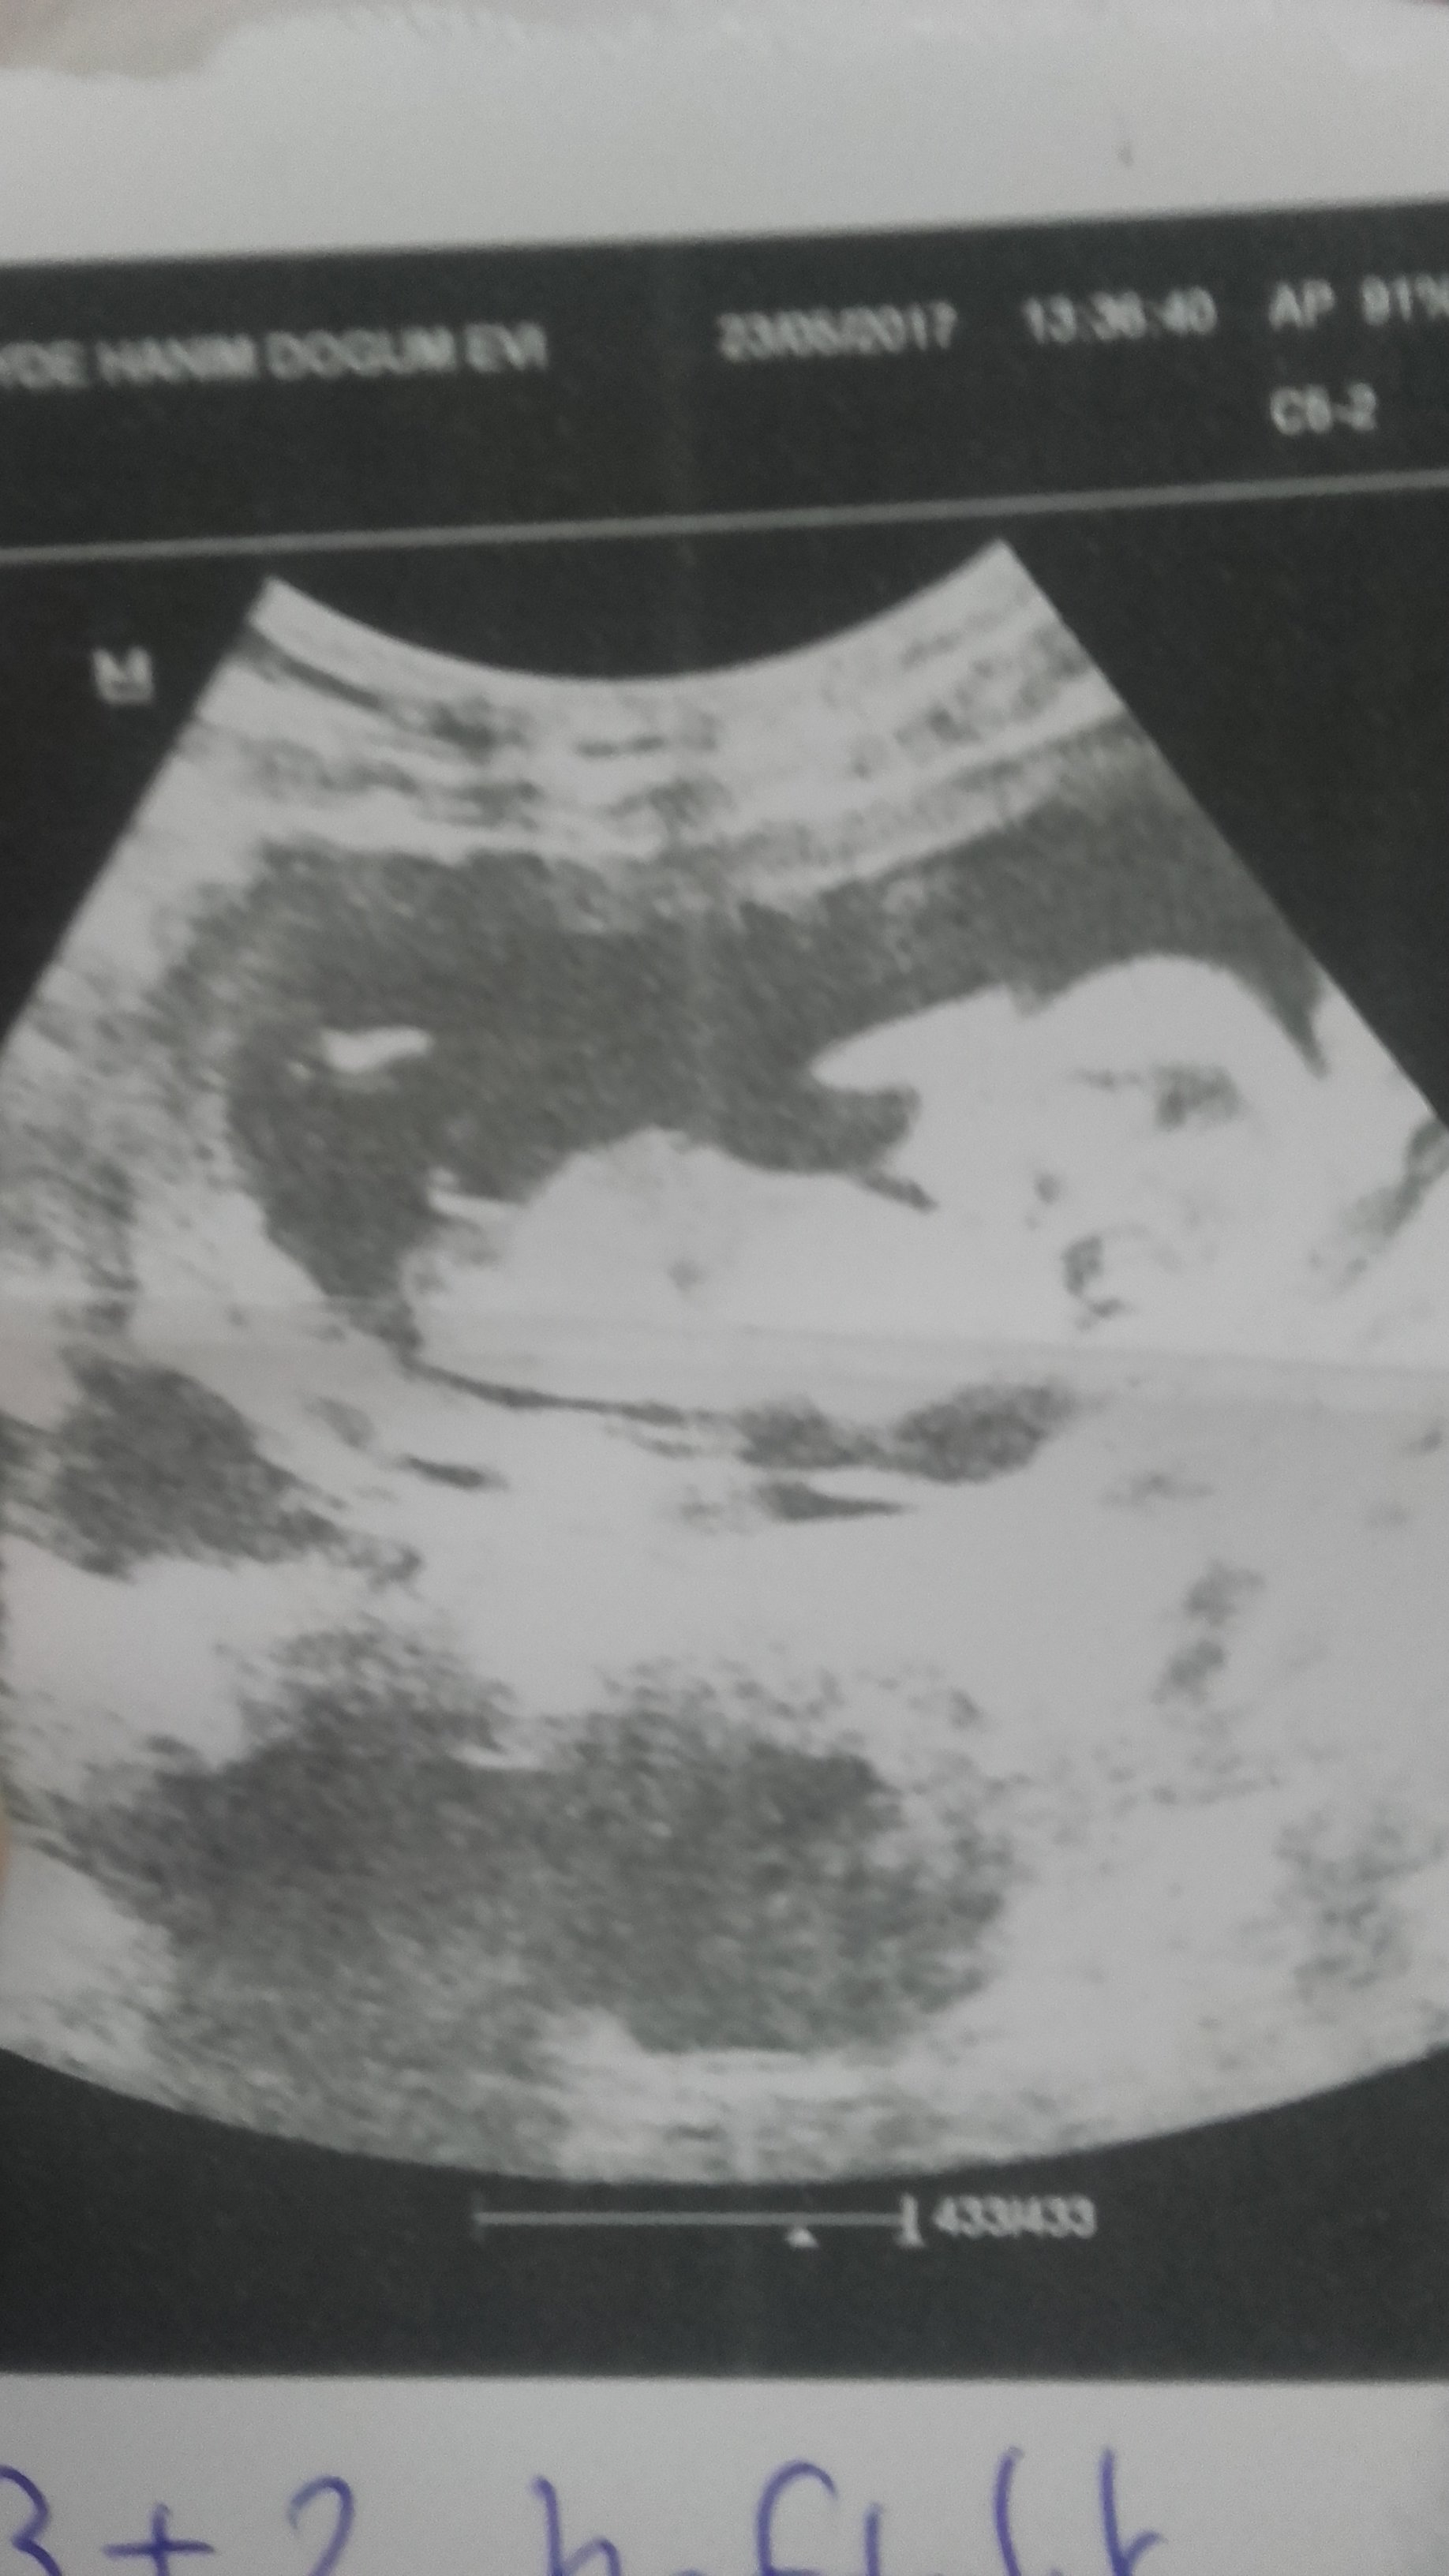

B Buglem2011 Yeni Üye Üye 26 Mayıs 2017 #285 Ekli dosyayı görüntüle 76905 Ekli dosyayı görüntüle 76906 sonunda yükledim banada yorum yaparmısınız tşkler şimdiden

Ekli dosyayı görüntüle 76905 Ekli dosyayı görüntüle 76906 sonunda yükledim banada yorum yaparmısınız tşkler şimdiden

HemşireniZ Aktif Üye Üye 26 Mayıs 2017 #287 Merhaba çıkıntının üzeri işaretli emin olmamakla birlikte bebeğinizin cinsiyetini kız olarak düşünüyorum.

Merhaba çıkıntının üzeri işaretli emin olmamakla birlikte bebeğinizin cinsiyetini kız olarak düşünüyorum.